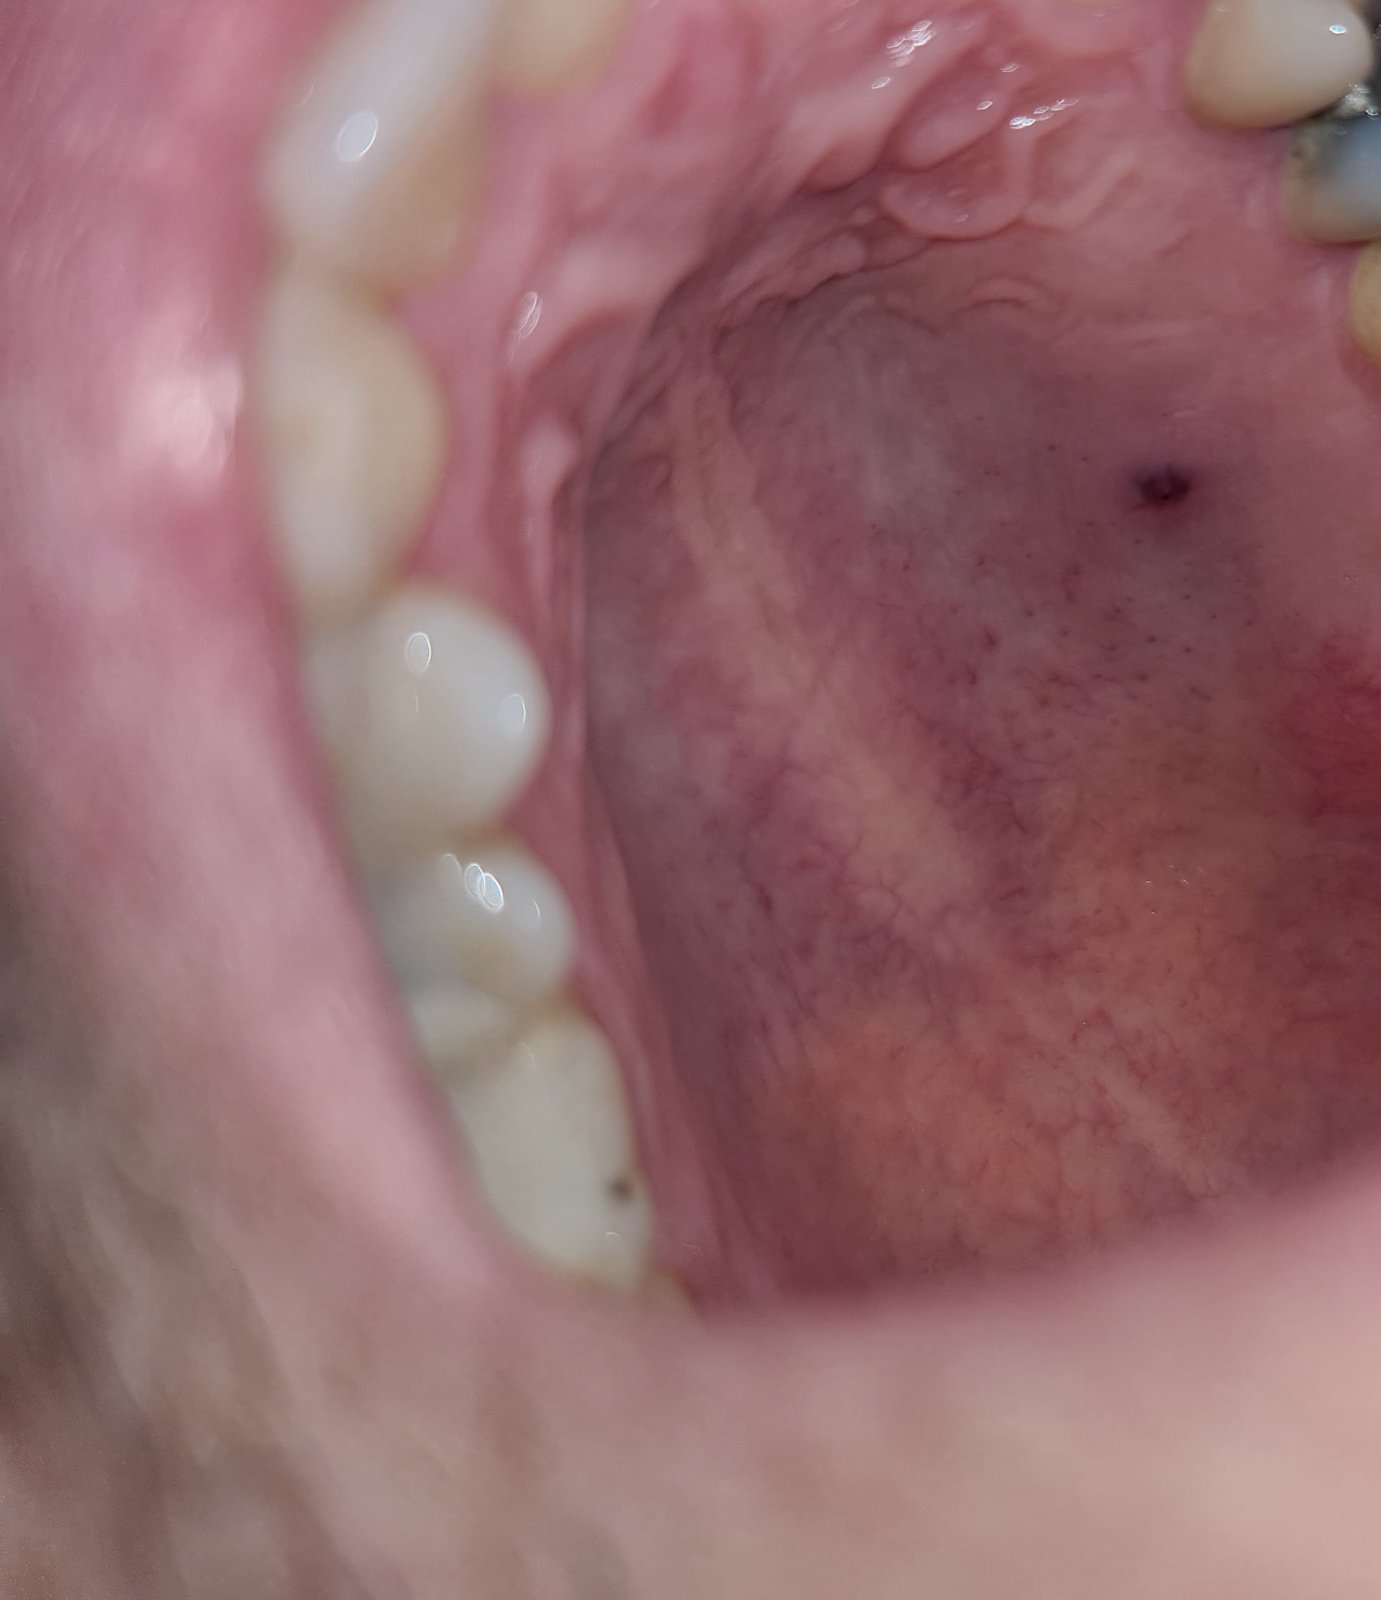

Ahojte už par dni ma bolela akoby hrčka na podnebí akoby herpes v ustach, dnes sa urobila hrčka, manželka to stlačilq tyčinkou akoby to vyšlo ale hovorila, že to vyzeralo ako niečo ostré no však nic ztade nevytiahla.

Mohla to byť nejaka afta prasklo ti to a teraz to maš krvnu bodku to ti zmizne